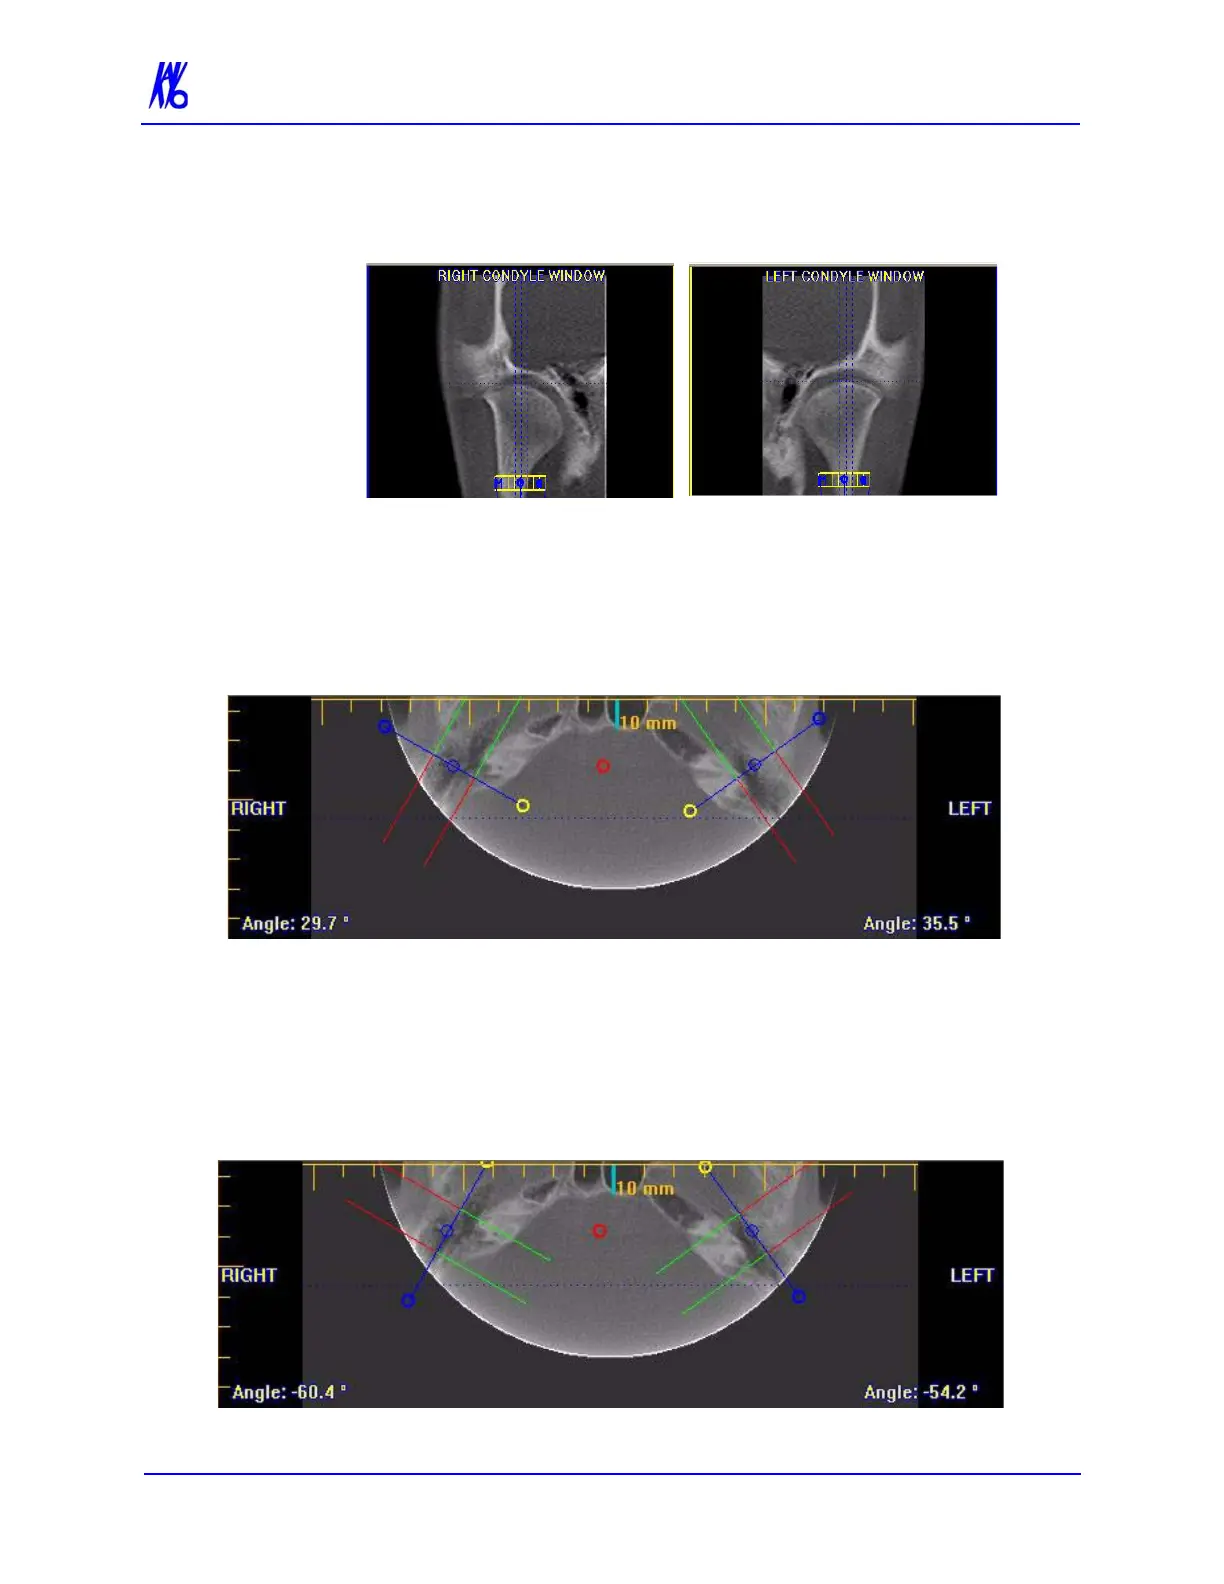

3. Drag center (O) tools from the RIGHT and/or LEFT CONDYLE

WINDOWS to move the slice locations of the cross section

views.

5. Drag the center blue circles on the Axial View to move the

corresponding Condyle Map.

6. Drag the yellow and blue end circles to adjust the angle of each

Condyle Map.

Green markings indicate the anterior of the Condyle.

Red markings indicate the posterior of the Condyle.

7. To create Coronal Slices, click the red circle.